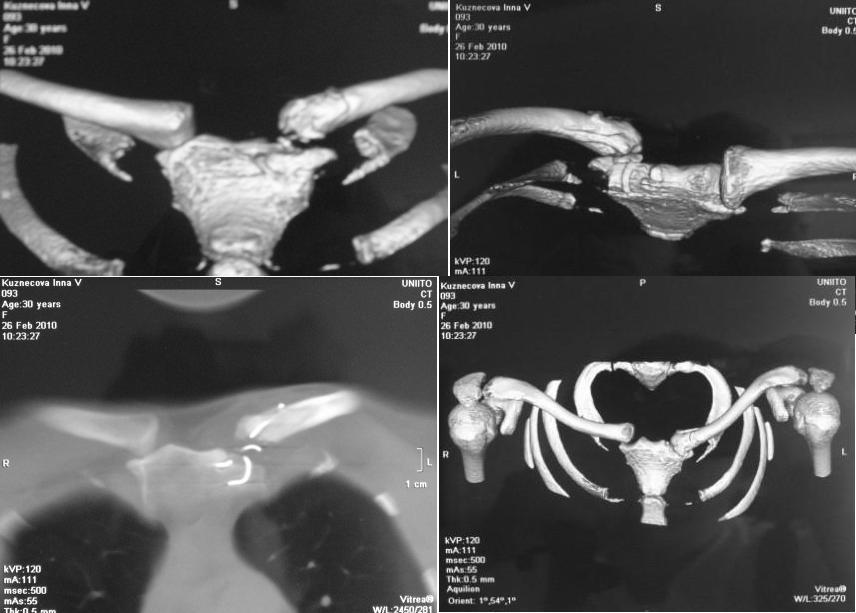

Пациентка К., 1979г.р., при ДТП, 15.07.09г. получила вывих грудинного конца левой ключицы. По месту жительства выполнено:

20.07.09г. шов лавсаном с фиксацией 8-образной ватно-марлевой повязкой с рецидивом вывиха грудинного конца ключицы;в сентябре 2009г. повторный шов лавсаном с фиксацией 8-образной ватно-марлевой повязкой с рецидивом вывиха грудинного конца ключицы,в ноябре 2009г. остеосинтез проволочной петлей и фиксацией торакобрахиальной гипсовой повязкой с последующим разрывом проволоки и рецидивом вывиха грудинного конца ключицы.29.12.09г. была выписана к труду. Работа пациентки связана с физическими нагрузками. В настоящее время предъявляет жалобы на деформацию и появление болей при движениях руки в грудино-ключичном сочленении слева. Локально: левое надплечье укорочено. Имеется выстояние грудинного конца ключицы кпереди и кнутри, которое при движении руки увеличивается и при этом появляется болезненность и хруст в грудино-ключичном сочленении слева. Пальпация грудино-ключичного сочленения безболезненная. Движения в левом плечевом суставе не ограниченные. Мышечная сила сохранная. Сосудистых и чувствительных расстройств нет.Диагноз: застарелый передневнутренний подвывих грудинного конца левой ключицы. Сросшийся перелом грудинного конца левой ключицы. Частичный дефект суставного конца левой ключицы.На КТ от 26.02.10г. диастаз между суставной поверхностью грудины и левой ключицей составляет 0,8-0,9см. Вопросы: Есть ли необходимость в оперативном вмешательстве?Вид хирургического пособия?Фиксация?